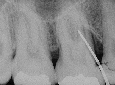

初診時の正中初診時

2年後の正中二年後